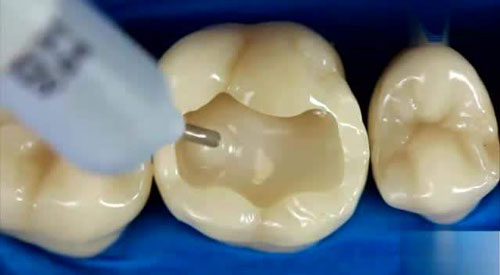

复合树脂。这是一种牙齿色的填充材料,由于其美学特性而越来越受欢迎。该材料以逐层方式施加,并且每层通过暴露于固化光来设定。对于复合填充,牙医不需要创建腔的特定形状。

• 在完全去除腐烂之后,清洁腔体并施加复合树脂层。复合材料是用于前牙的理想填充材料类型,具有更高强度的更坚韧的混合物可用于后牙。